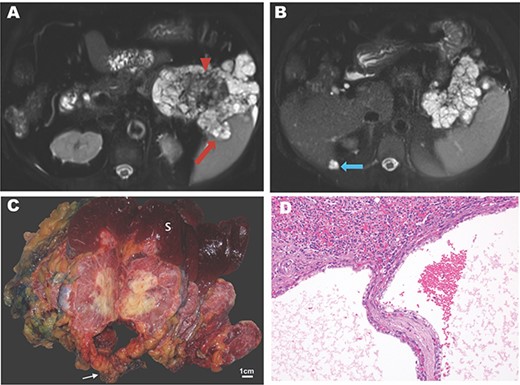

A 74-year-old woman with a history of hypertension, hypercholesterolemia and gastroesophageal reflux presented with dyspnea and uncontrolled hypertension. Her past surgical history included wrist surgery and a cholecystectomy. Family history was notable for leukemia, lung, extrahepatic bile duct and colon cancer. Other symptoms included early satiety and increased gastroesophageal reflux. Pulmonary embolism was initially suspected, but computed tomography instead showed a 10 cm, multi-cystic, partially calcified mass in the tail of pancreas. Percutaneous biopsy was performed revealing an SCN. Magnetic resonance (MR) imaging revealed an 11.5-cm lesion in the pancreatic body and tail. On T2-weighted images, a microcystic mass with a bosselated surface and a central dark scar (Fig. 1A) was seen. Malignancy was suspected on the basis of invasion into the splenic parenchyma and a cystic lesion adjacent to the liver with similar features (Fig. 1B).

Imaging and pathology of serous cystadenocarcinoma of the pancreas. (A) T2-weighted MR image showing microcysic lesion with invasion into spleen (red arrow) and central dark scar (arrowhead) with (B) peritoneal lesion at inferior tip of the liver (blue arrow). (C) Gross specimen photograph demonstrating the large pancreatic mass (white arrow) with invasion into the spleen (S) and central necrosis (scale bar, 1 cm). (D) Photomicrograph demonstrating invasion of the splenic parenchyma (superior, H&E, 20×).

The patient underwent a distal subtotal pancreatectomy/splenectomy and resection of the cystic lesion adjacent to the liver in 2018. Surgical pathology revealed an 11.5 × 10.0 × 9.0 cm mass that largely replaced the pancreatic body and tail. This mass had a pinkish, glistening, solid and cystic cut surface with central chalky white necrosis (Fig. 1C). This lesion was grossly adherent to the splenic hilum. The surgical margins were widely uninvolved by the tumor. Microscopically, the tumor had the classic morphology of a serous cystic neoplasm of the pancreas with cysts lined by cuboidal to flattened cells with bland, central, round nuclei and abundant clear cytoplasm. PAS stains demonstrated abundant glycogen. There were large areas of coagulative necrosis, and the tumor focally invaded the splenic parenchyma grossly (Fig. 1C) and microscopically (Fig. 1D). Mitotic figures were not identified. The separately submitted perihepatic nodule showed identical morphology, consistent with a distant metastasis. Altogether, these findings were diagnostic of a serous cystadenocarcinoma. An outside consultation was obtained from the Johns Hopkins Department of Pathology which confirmed the diagnosis.